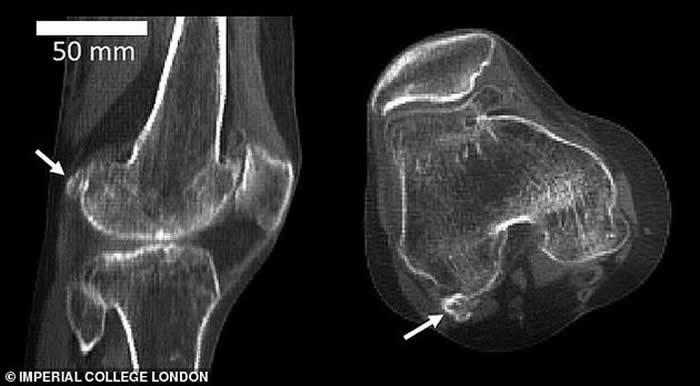

豆骨(fabella),是位于膝盖后方肌腱中的一块小骨骼,目前它在人体存在的概率是100年前的3倍,全球五分之二居民都长有豆骨。

图中显示3个不同膝骨样本存在不同大小的豆骨。科学家发现1918年全球11.2%居民体内存在豆骨,但截至2018年,全球39%居民体内存在豆骨。

英国伦敦帝国理工学院的研究人员回顾了过去150多年进行的2.1万多项科学研究,其中包括研究人员扫描和解剖鉴定发现豆骨的存在。他们从中发现1918年全球11.2%居民体内存在豆骨,但依据发表在《解剖学杂志》的这篇评论报告,截至2018年,全球39%居民体内存在豆骨。

伯托姆博士称,当远古灵长目动物进化成大猿和人类,我们似乎已不再需要豆骨,现在它只会给我们带来麻烦,但有趣的是,近年来人体出现豆骨的概率骤增。这项最新研究发表在《解剖学杂志》上,作者详细研究了25个国家21676个膝盖数据,最早的数据可追溯至1875年。这些膝盖数据来自多种渠道,其中包括:X射线、核磁共振扫描和局部解剖。